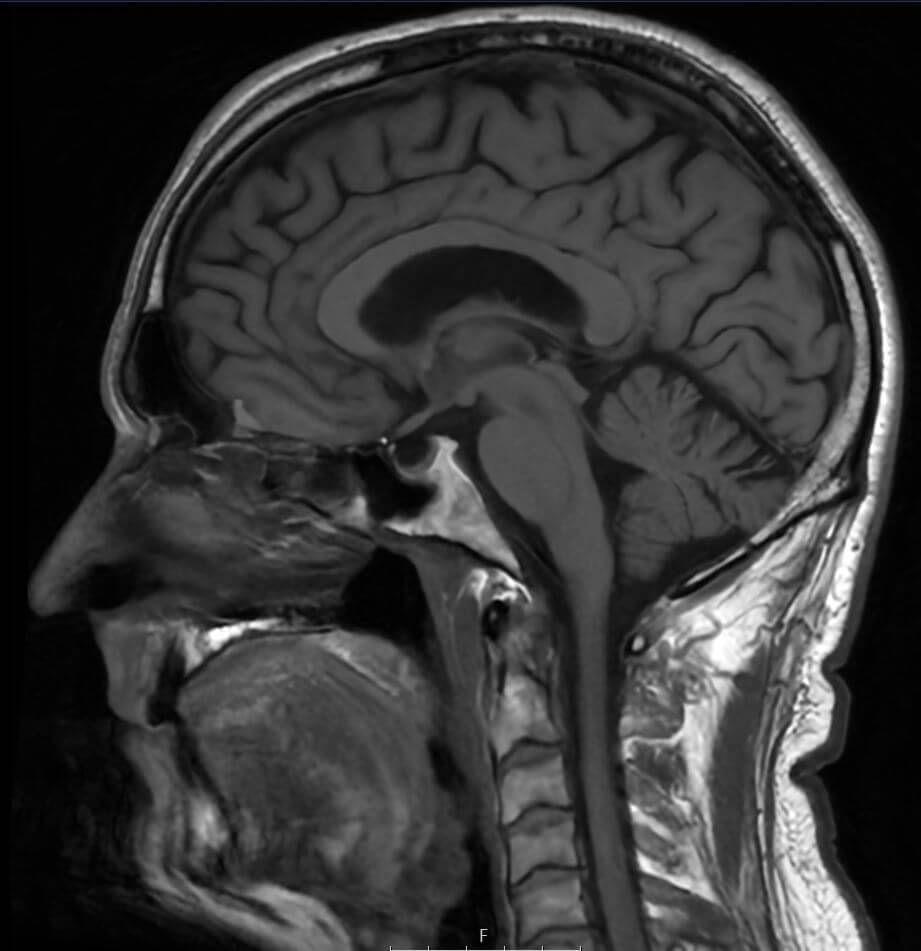

Hvad er en MR-scanning af hjernen?

Hjernen udgør sammen med rygmarven og hjernestammen kroppens centralnervesystem og styrer alle funktioner i kroppen. Alt fra dine tanker og tale til dine bevægelser og følelser er afhængig af hjernens komplekse netværk af nerveforbindelser. Derfor er det afgørende at værne om hjernens sundhed – også selvom du ikke oplever synlige symptomer.

En MR-scanning af hjernen er en avanceret billedteknik, der bruger magnetfelter og radiobølger til at skabe detaljerede billeder af hjernens strukturer. Metoden har været brugt siden 1980’erne og er i dag det foretrukne værktøj til at opdage forandringer og forhindre alvorlige konsekvenser.

Ved en MR-scanning tages omkring 2.000 detaljerede billeder, som giver et præcist indblik i hjernens anatomi, herunder:

- Hjernestammen og cerebrospinalvæsken, der omgiver hjernen og rygmarven

- Hjernebarken (den grå substans), som styrer kroppens funktioner

- Den hvide substans med nervebaner, der forbinder hjernens forskellige dele

Eksempler på MR-scanninger